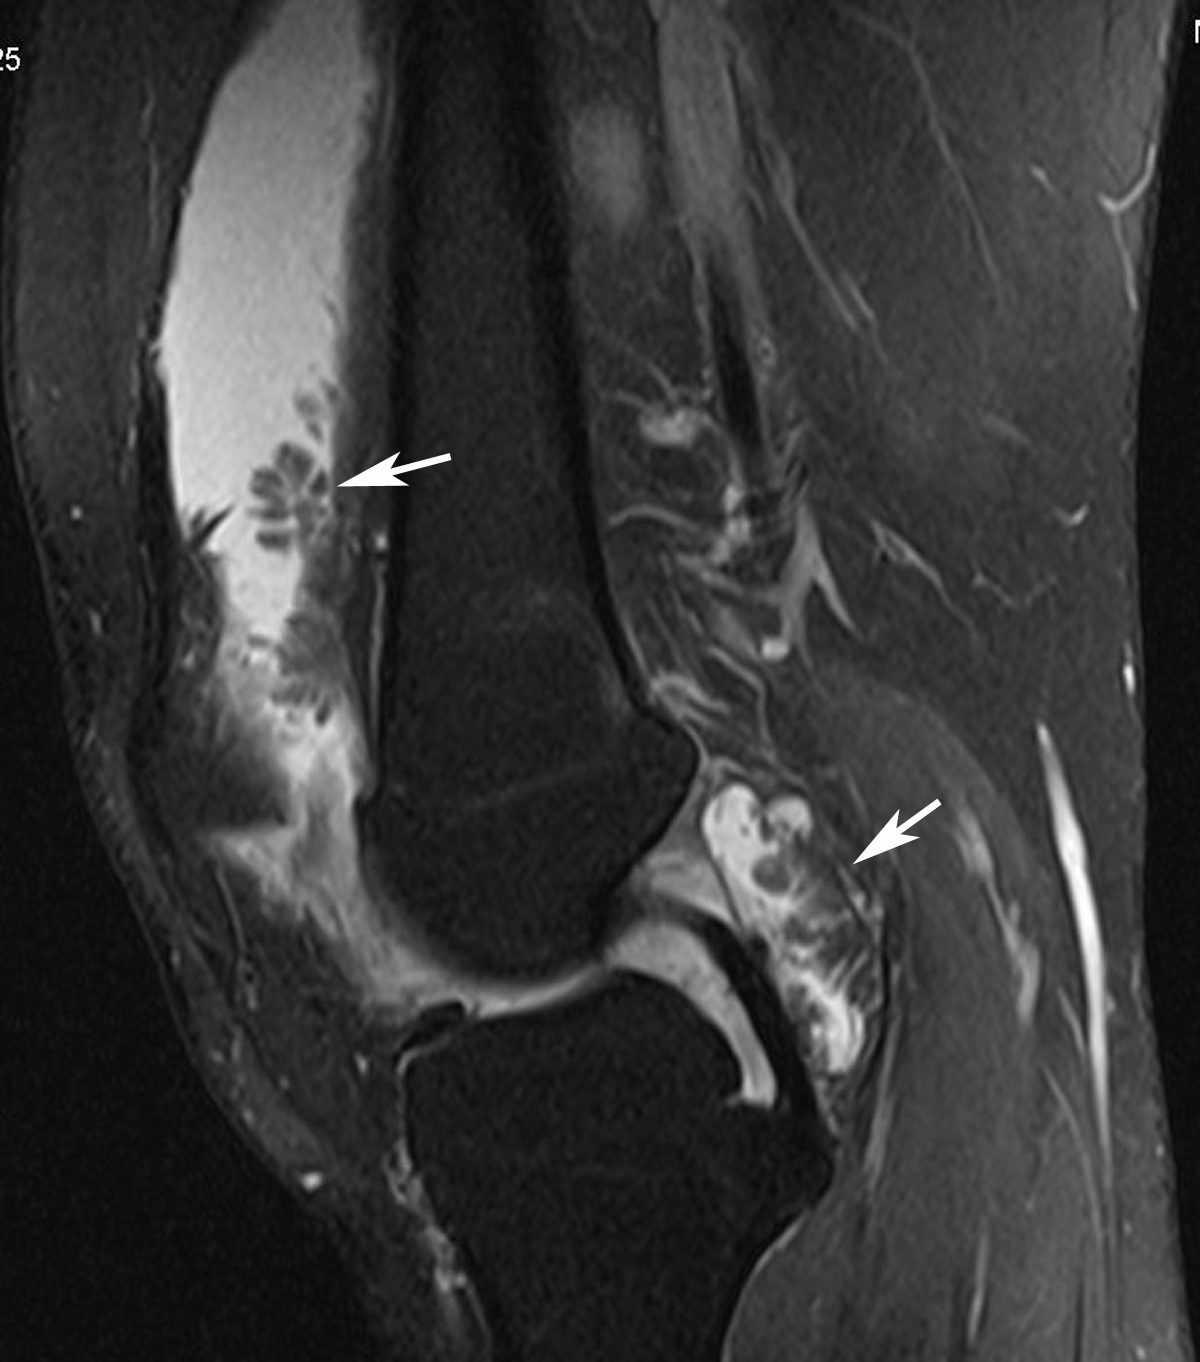

RADIODIAGNOSIS IMAGE COLLECTION Lipoma arborescens

From rakheeradimages.blogspot.com

RADIODIAGNOSIS IMAGE COLLECTION Lipoma arborescens Synovial Thickening Elbow Mri Synovial chondromatosis, pvns and rice bodies. mri reveals prominent diffuse villous or nodular proliferation of synovium and associated joint effusion. In a subgroup of patients, plicae, when thickened, may. Mri findings of synovial diseases. mri and ct or mr arthrography are useful tools in the diagnosis of elbow synovial fold. the differential diagnosis for the low intensity. Synovial Thickening Elbow Mri.